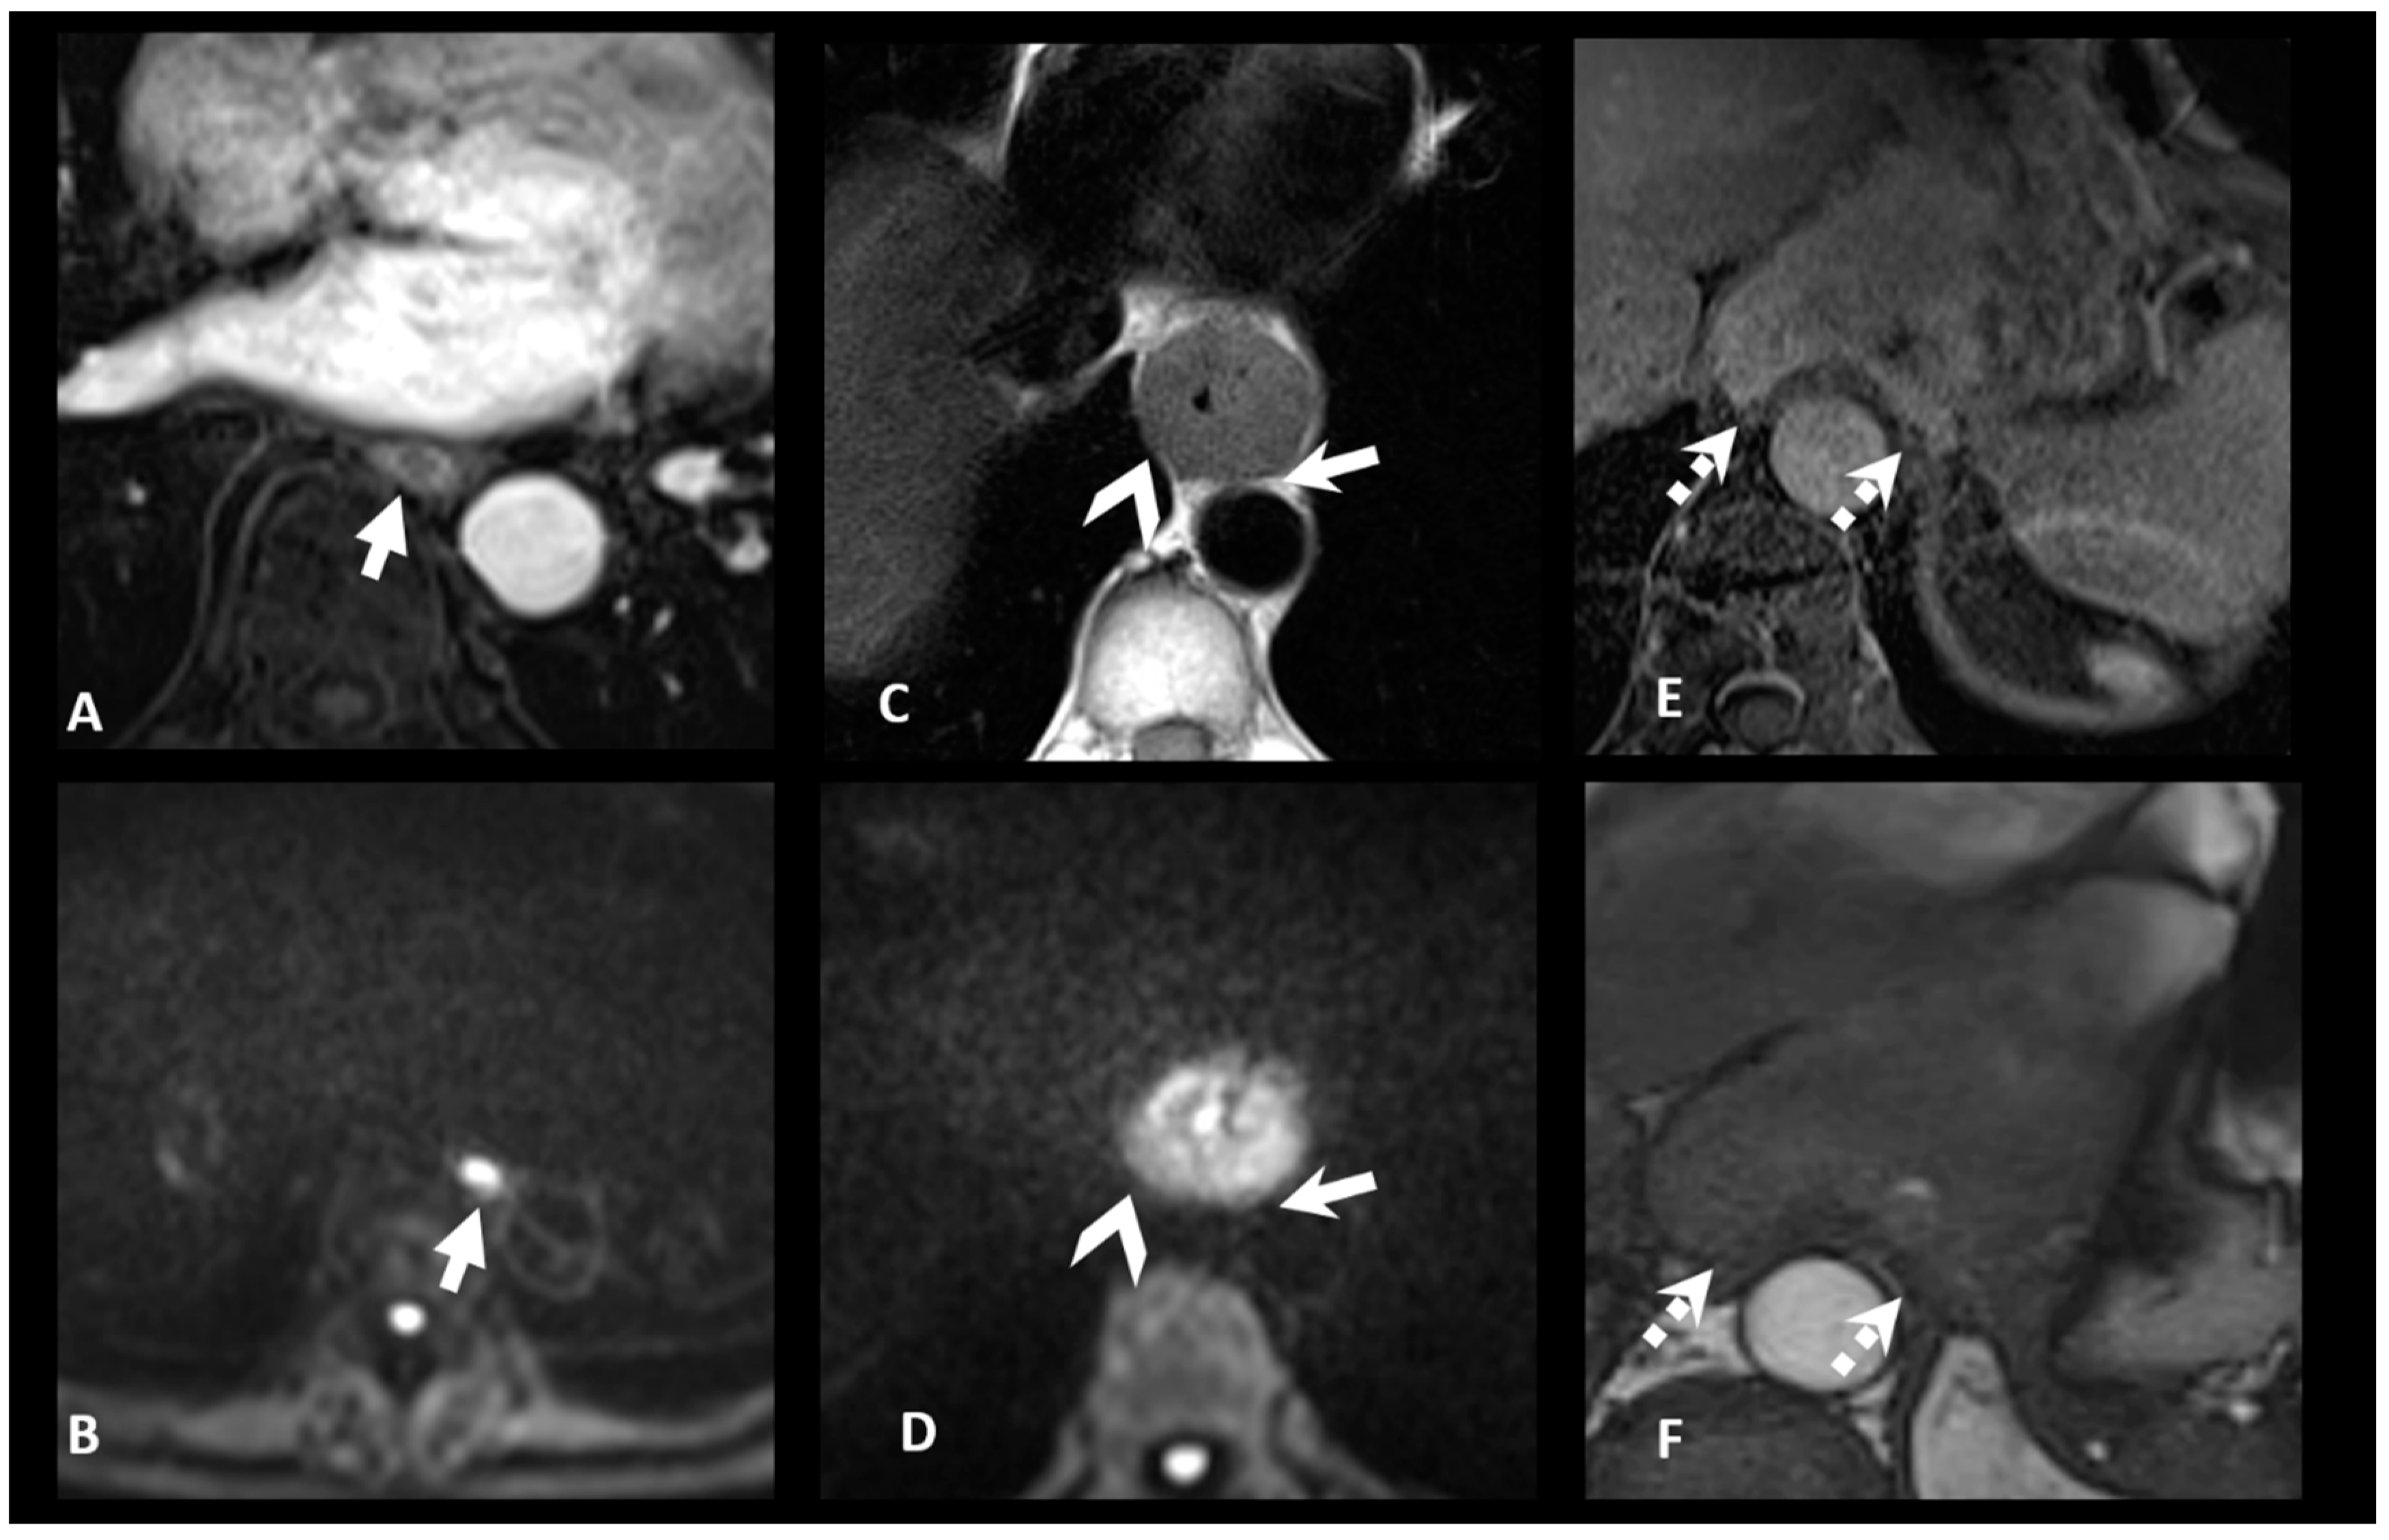

3.2. N Staging

| N+: Regional lymph nodes metastasis | MRI-N+: Round, Intermediate to high T2 signal, heterogeneous T1 Gd, >5 mm small axe |